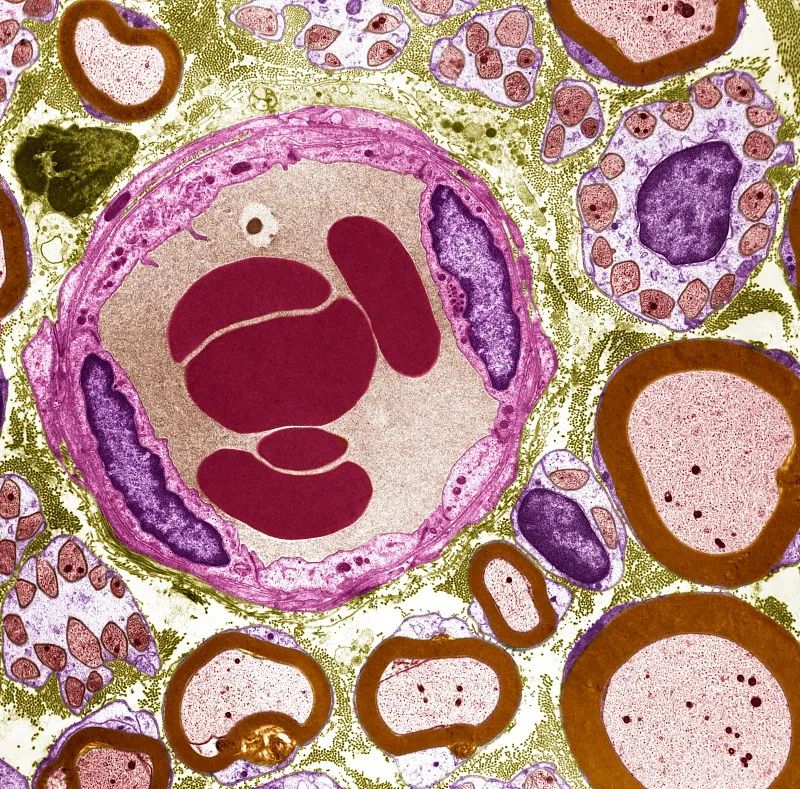

图片